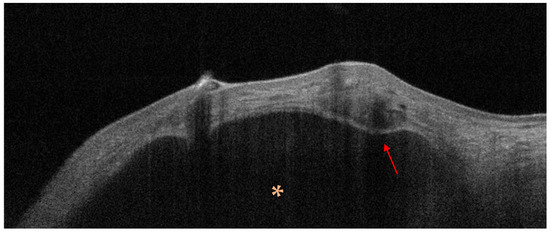

Our present Special Issue will focus on the latest advances in the management of cutaneous malignancies, including the use of various biomarkers, diagnostic devices, imaging techniques (dermoscopy, optical coherence tomography, high-frequency ultrasound, reflectance confocal microscopy, etc.), and novel treatment options. New concepts on early detection, genomic and molecular testing, approaches guiding treatment decisions, and the monitoring of the therapy of cutaneous malignancies are also within the scope. Novel findings on the use of artificial intelligence to enhance the diagnostics of cutaneous malignancies are also welcome. Teledermatology, alone or in combination with artificial intelligence, is also a rapidly developing technology that has a key role in the management of cutaneous malignancies; therefore, it is also included. New data on the background and factors contributing to the development of cutaneous malignancies are of special interest.